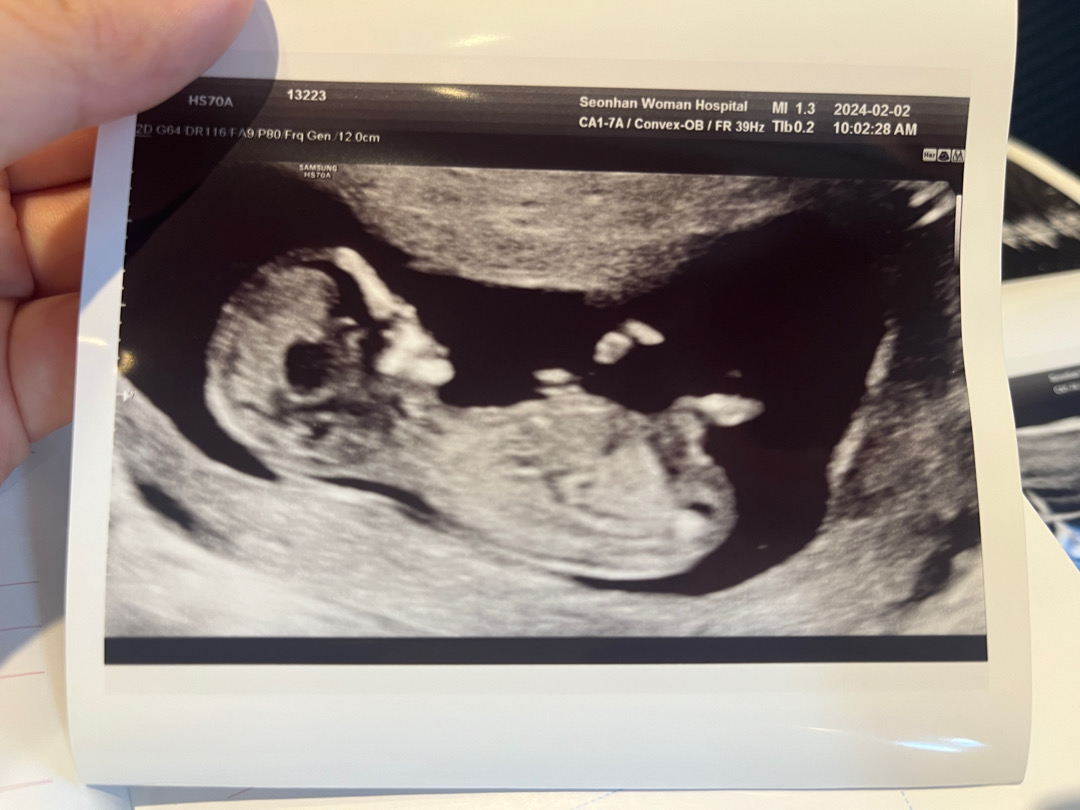

12주3일 각도법 여쭤봐요 💗

아직은 알수 없겠지만 혹시 잘 보시는분 답변 부탁드려요💗